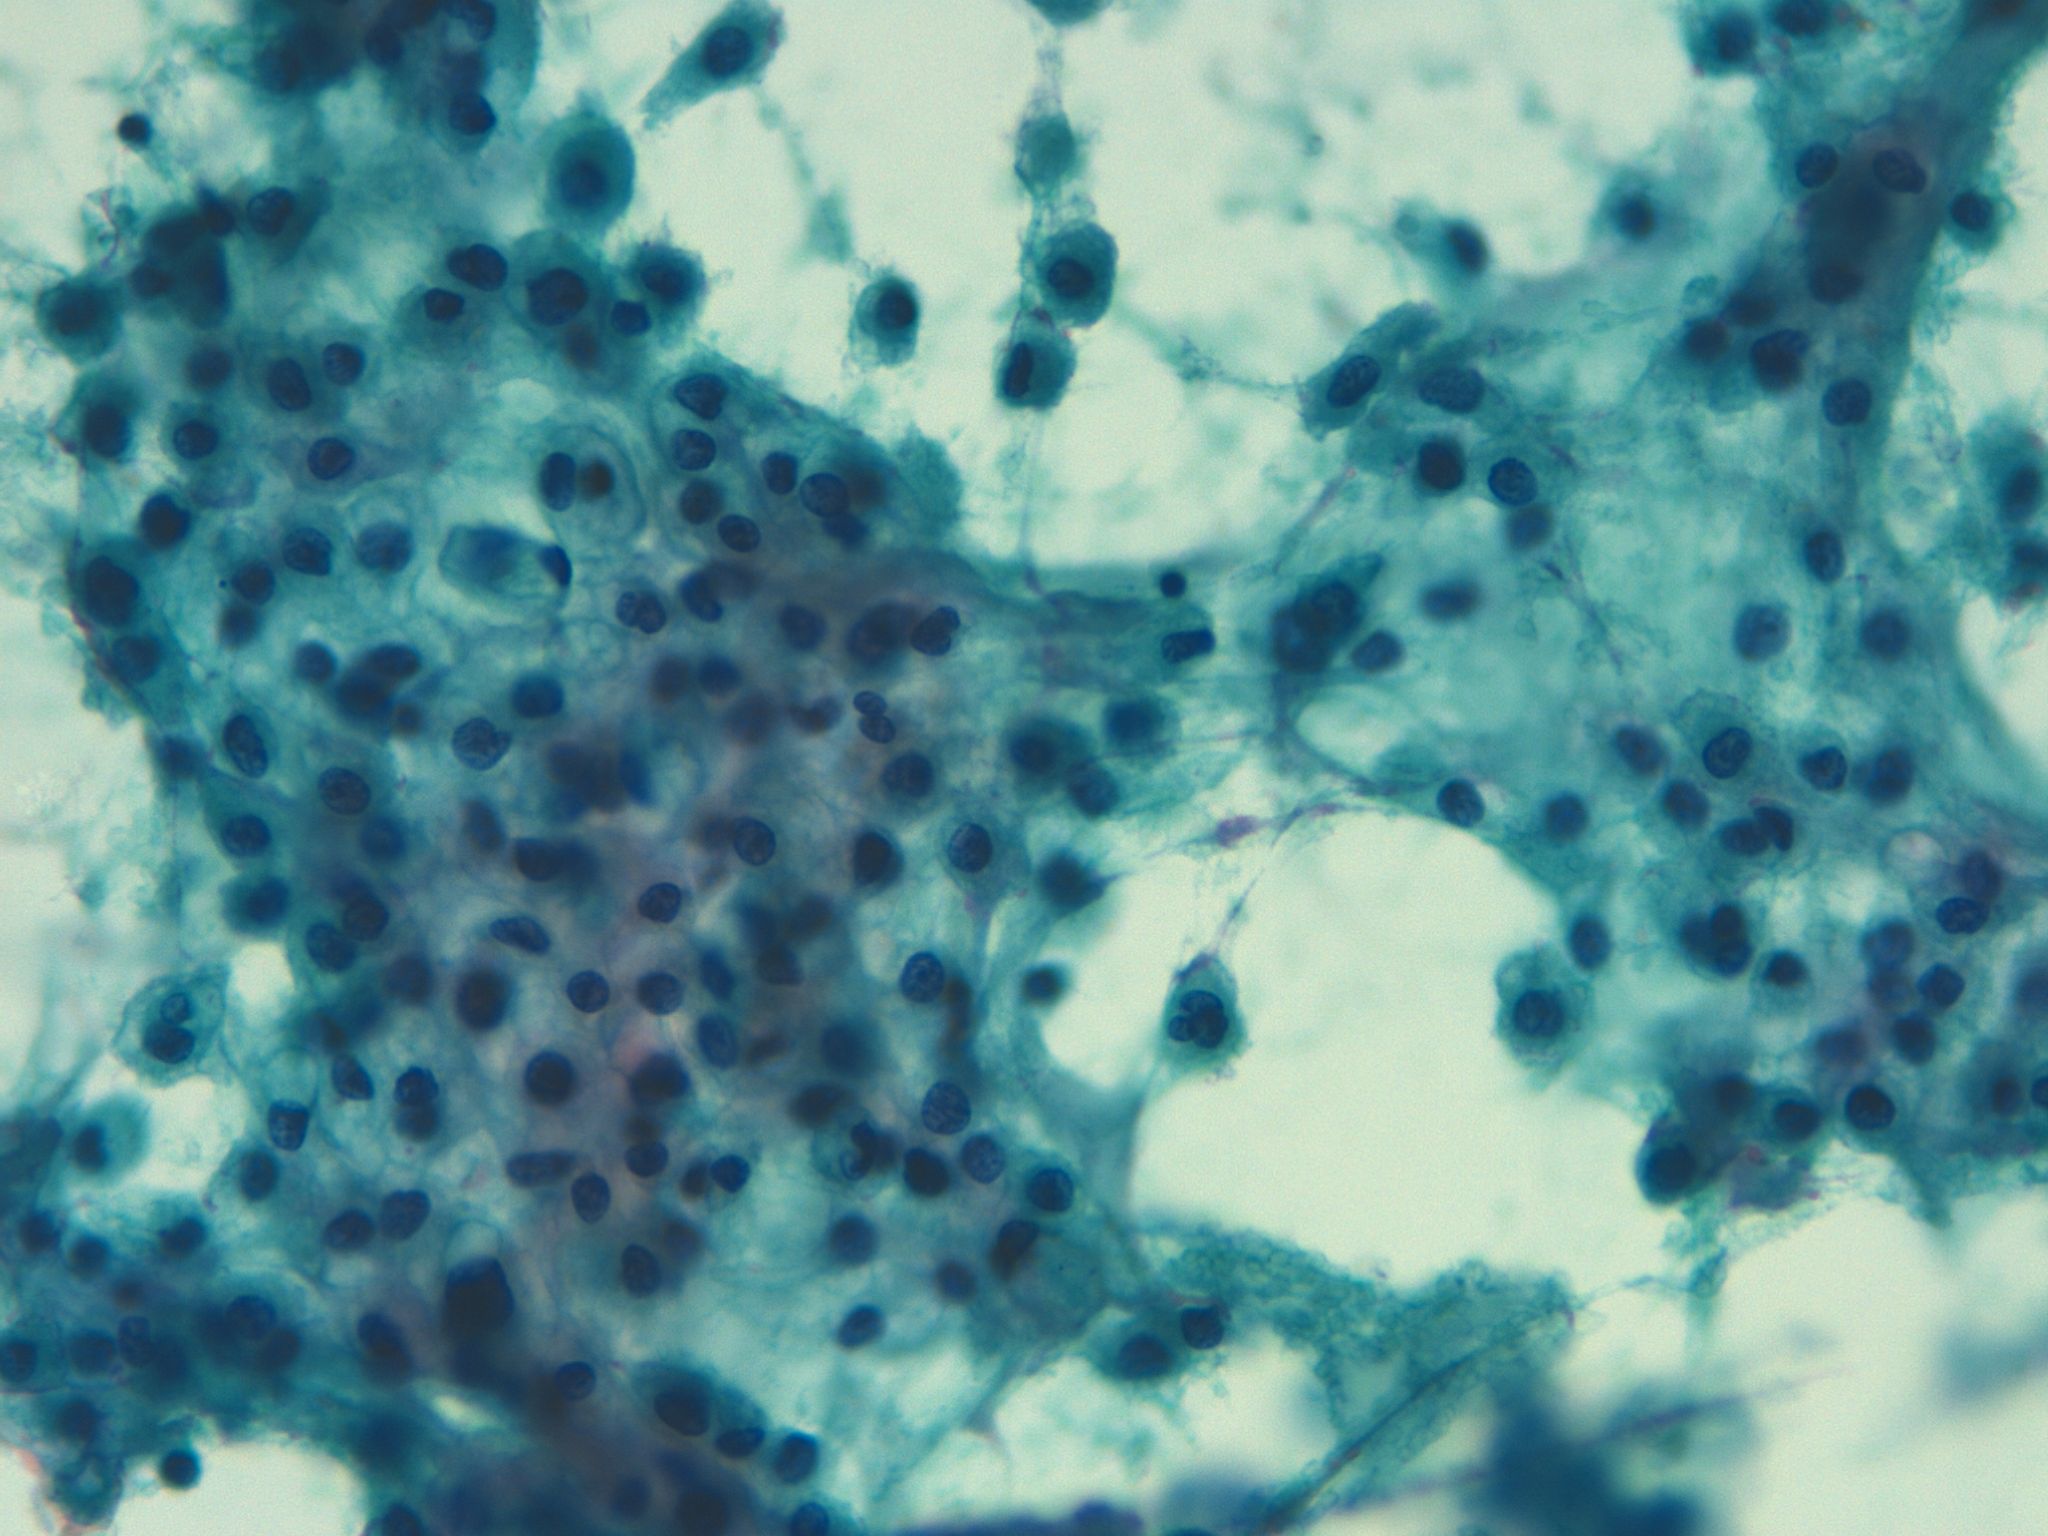

Dr. Ignacio Guasch, Dr. Edwin Mejía.

Hospital Germans Trias i Pujol, Badalona.

Hombre de 59 años, bronquítico crónico que refiere aumento del volumen mamario bilateral. Con una TC que informa masa tumoral en mediastino medio, voluminosa, sólido- quística, con extensa necrosis tumoral y adenopatías mediastínicas paratraqueales de tamaño significativo. Se realizar una PAAF guiada Ultrasonografía Ecobroncoscópica (EBUS) para el diagnóstico definitivo.